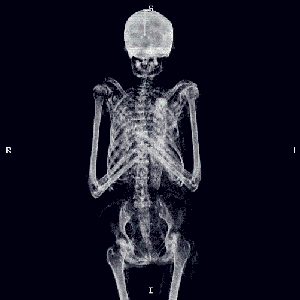

經過X線片檢查

醫(yī)生并沒有發(fā)現明顯的異常

醫(yī)生根據邢大叔的癥狀

推薦他進行肌骨超聲檢查